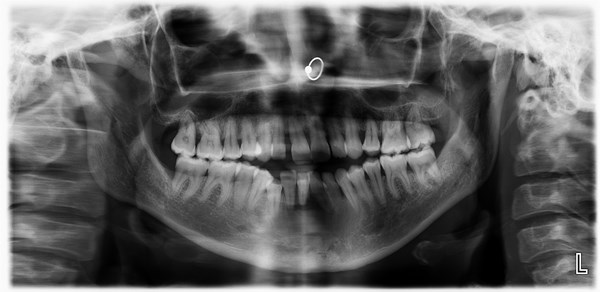

Tengo periodontitis en el incisivo inf. Y el hueso no lo sostiene. Extraigo el diente?

Parece que se sujeta el diente solo por las encías que van en retroceso y la masa osea no sujeta el incisivo. ¿He de quitarme el diente? No tengo ninguna infección en la raíz, sí mala oclusión y burxismo. El dentista me recomienda sacarlo, esperar que regenere el hueso para poner un implante y de mientras ponerme uno temporal removible. ¿No se puede conservar el diente y implantar hueso del maxilar?